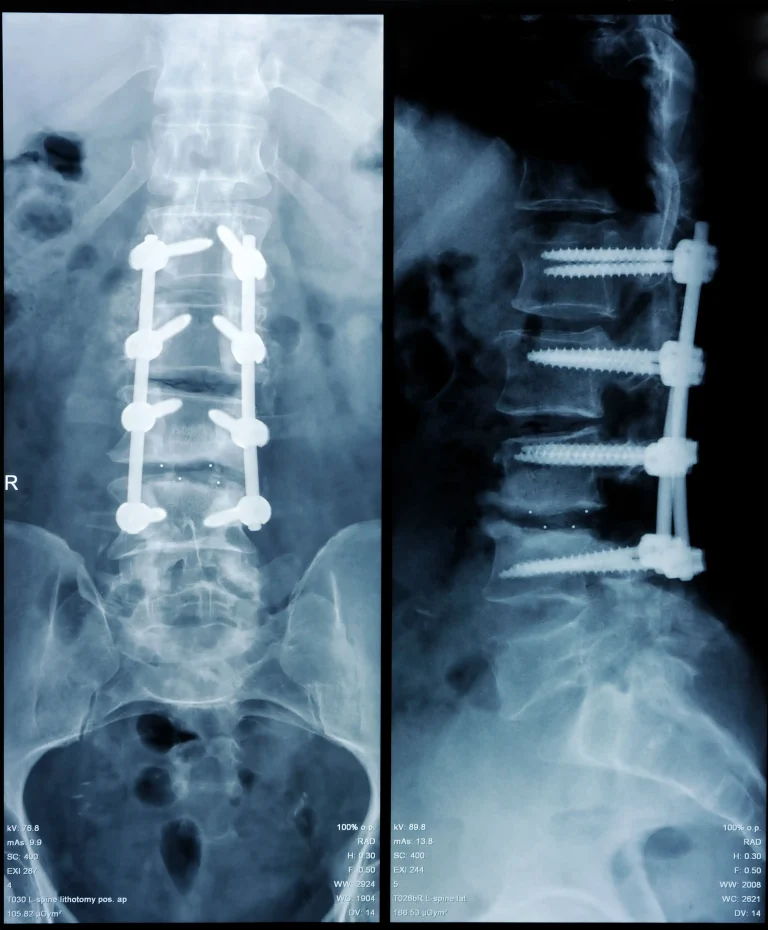

X-ray showing spinal fusion with screws and rods from front and side views.

Back Pain Gets Worse

Back pain becomes worse after laminectomy. Fusion will be recommended.

Spinal Fusion Often Required

Destruction of normal stabilizing bones including lamina and spinous process by the surgeon during laminectomy.

90%+ Need Additional Surgery

Additional surgery will be necessary in over 90% of patients having laminectomy.